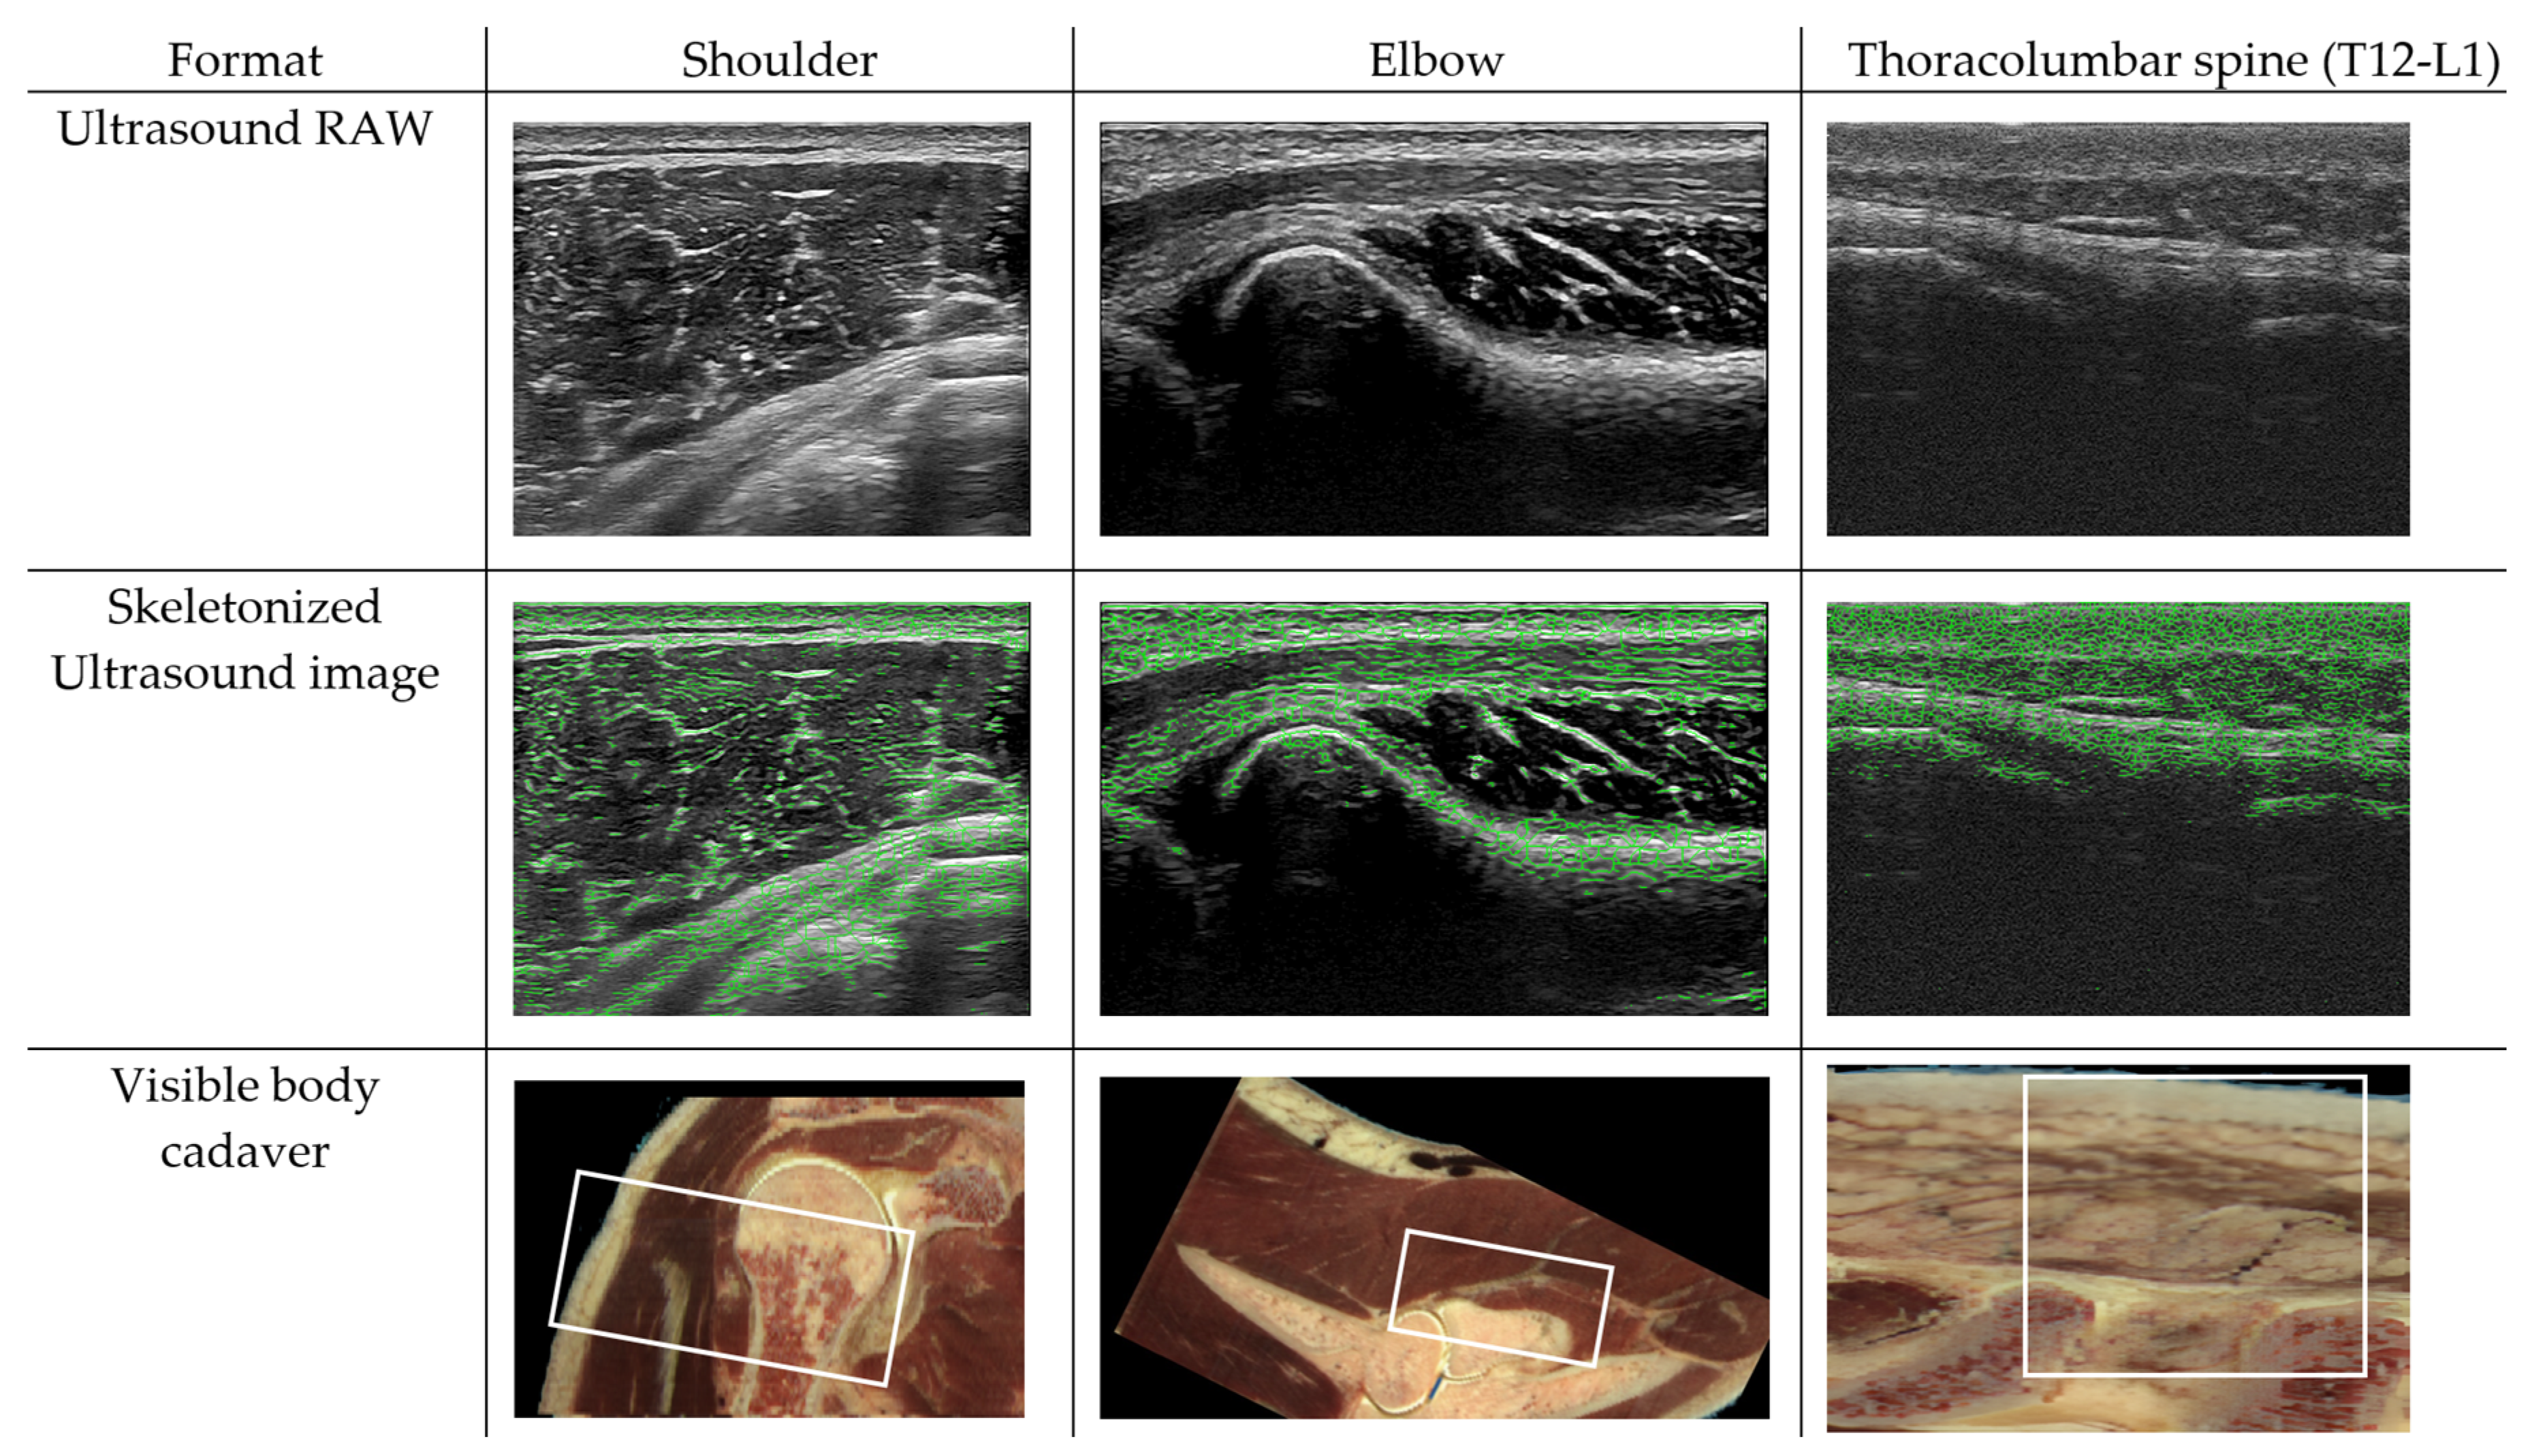

4. Proof of Concept: Ultrasound-Based Evaluation